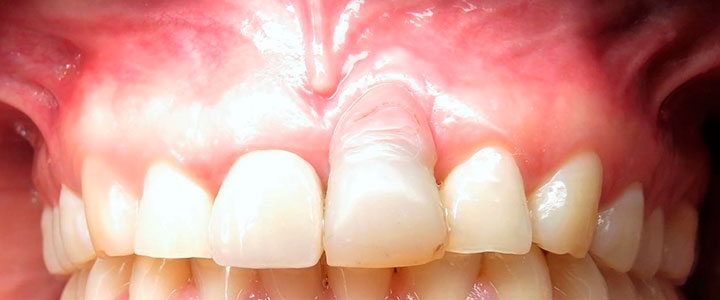

Se empezó a hacer la distracción, primero con un arco recto y posteriormente con elásticos haciendo el recorte con el borde incisal conforme se va bajando el implante con el bloque óseo.

Al término de la distracción dejamos pasar tres meses con una férula en acrílico. En el diente 21 que habíamos visto en la radiografía un problema de un absceso periapical y periodontal.